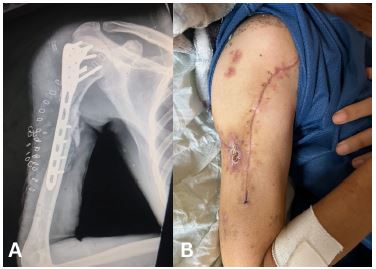

A 22-year-old male presented with a traumatic brain injury, a right-sided haemothorax, and a Gustilo-Anderson Grade III open fracture of the right proximal humerus caused by a gunshot injury. The patient received intercostal tube drainage and underwent ORIF (Figure 3A), primary wound closure, and received a course of IV Ceftriaxone. He was admitted to the ICU for 3 weeks and the wound was found to have healed by week 2 (Figure 3B). Unfortunately, the patient failed trials of extubation and passed away on week 4.

Figure 3: (A) Anteroposterior view radiograph of the comminuted fracture of the right proximal humerus with plate and nails visible in situ. (B) Clinical photograph of the healed wound.